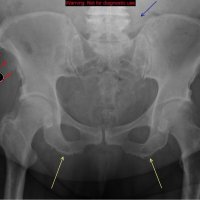

AP radiograph of the pelvis reveals extensive fluffy or "whiskering" enthesopathy of the iliac crests (red arrows), ischial tuberosities (yellow arrows), and the trochanters (black arrows). Note is also made of ossification of the iliolumbar ligament (blue arrow). Importantly, both sacroiliac joints appear normal. These findings are in keeping with diffuse idiopathic skeletal hyperostosis (DISH).

Diffuse Idiopathic skeletal hyperostosis (DISH) is a bone-forming diathesis primarily affecting the spine, with ossification of tendons and ligaments. Most of us are familiar with the spinal findings; however there are extraspinal manifestations as well such as hyperostosis at ligament attachments in the pelvis, calcaneus, tarsal bones, ulnar olecranon and patella.

Usually these are incidental findings without significant morbidity.